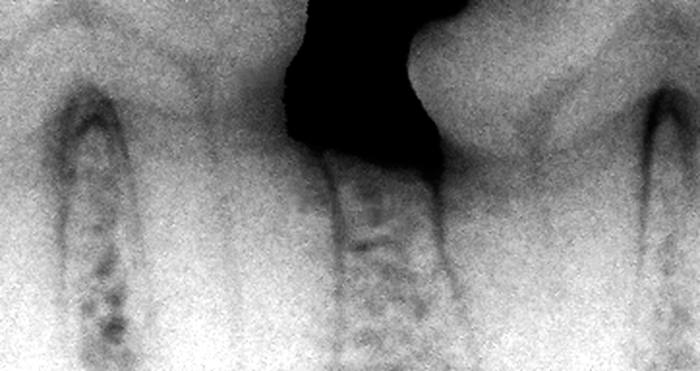

Radiograph showing less than 25% bone loss horizontally

Early disease defined by attachment loss of up to 25%. Sulcus deepened by disease with periodontal ligament (PL), alveolar bone crest and cementum all exposed to bacteria. These tissues recede away from the infection leading directly to attachment loss.